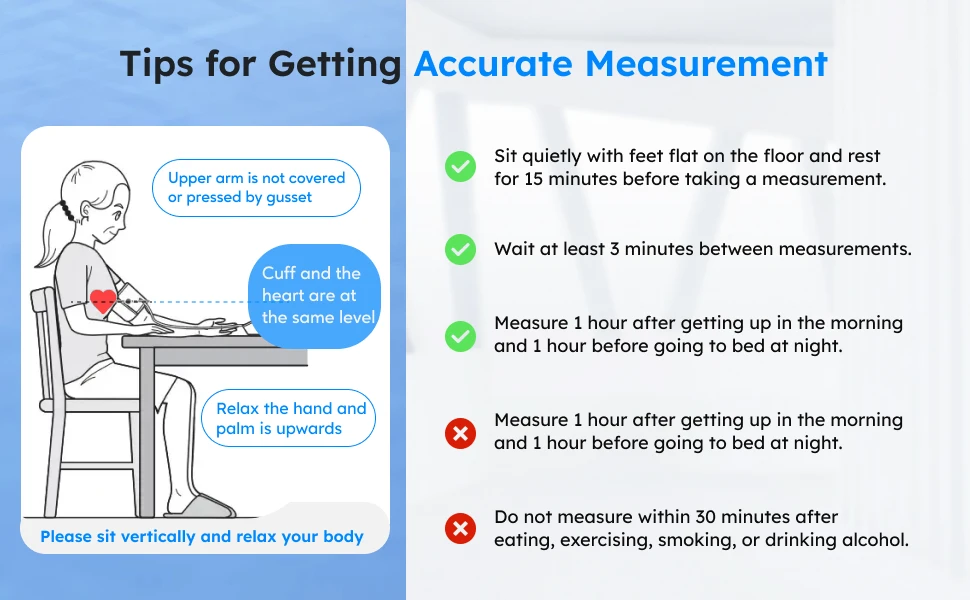

How to use it:

Wear the arm cuff

Make the nozzle of the arm cuff point to your forearm,arm cuff is 1-2cm higher than the elbow joint.Red-marked area on the arm cuff point to your mid-finger,please keep the nozzle upwards.

Measuring Condition:

1.Keep back straight, relax

2.Expose your upper arm or wear thin clothe only